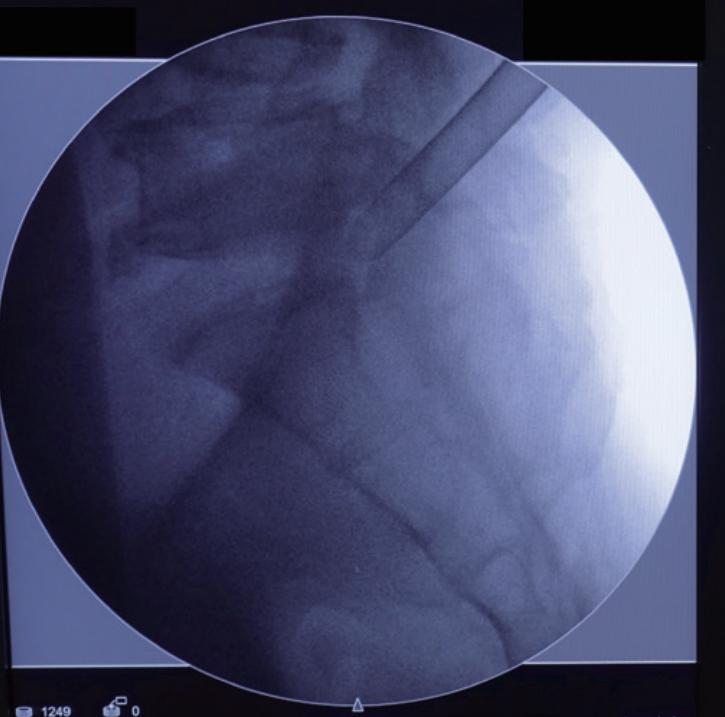

图2:侧视图示通道停靠在上关节突和椎弓根交界处;正位图示通道位于椎间孔的外侧边缘。